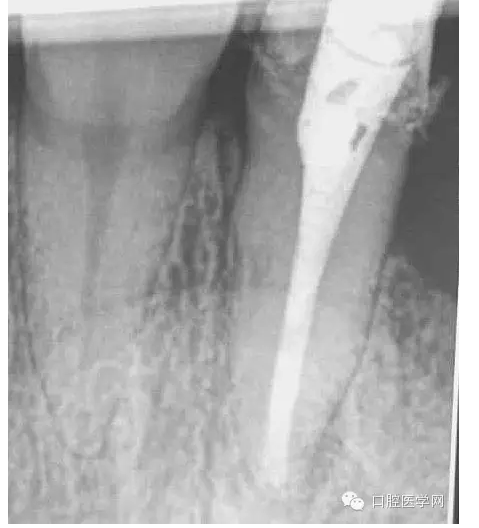

4.準(zhǔn)備放置橡皮障(由于拍片是較遠(yuǎn),所以,橡皮章暫時(shí)取下),去除暫封材料。在顯微鏡放大視野中,蔣調(diào)拌好MTA輸送至根尖部。

5.待MTA凝固后進(jìn)行熱牙膠充填。

一年前接診的病例,在各級(jí)門診診所轉(zhuǎn)診三次,不見(jiàn)好轉(zhuǎn)。最后到本院 !觀察一年以后的效果!